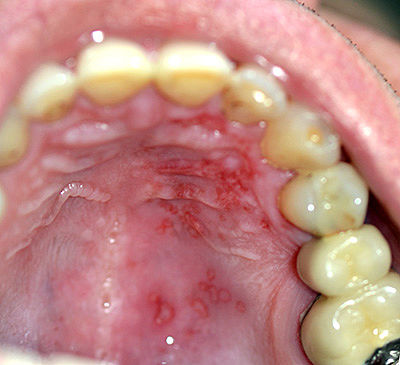

Добрый вечер.в четверг утром обожгла верхнее нёбо горячим кофе. Сначала был небольшой дискомфорт,потом сильнее. Мазала Метрогил, Холисал. Брызгала Фортезу,полоскала шалфеем. Вчера были на природе и я твердой пищей+специи+алкоголь наверное усугубила ситуацию. Сегодня посмотрела с фонариком,а там вверху,начиная от зуба по десне и к середине нёба все в мелкую красную точечку. Болит ужасно,есть и пить ничего не могу,болит прям пол головы и ухо.,..😭что это может быть,чем себе помочь,я боюсь....,

Я не хочу пугать и скидывать его фото . Вот похожее балл а начале .... потом вообще страх.

У меня не совсем похоже. Только цвет совпадает,а вот на вид как мелкая мелкая сыпь красные точечки.

Начало было как вы описываете , это на фото стадия 2 . 3 - сплошное пятно. Боли - крови и и д .